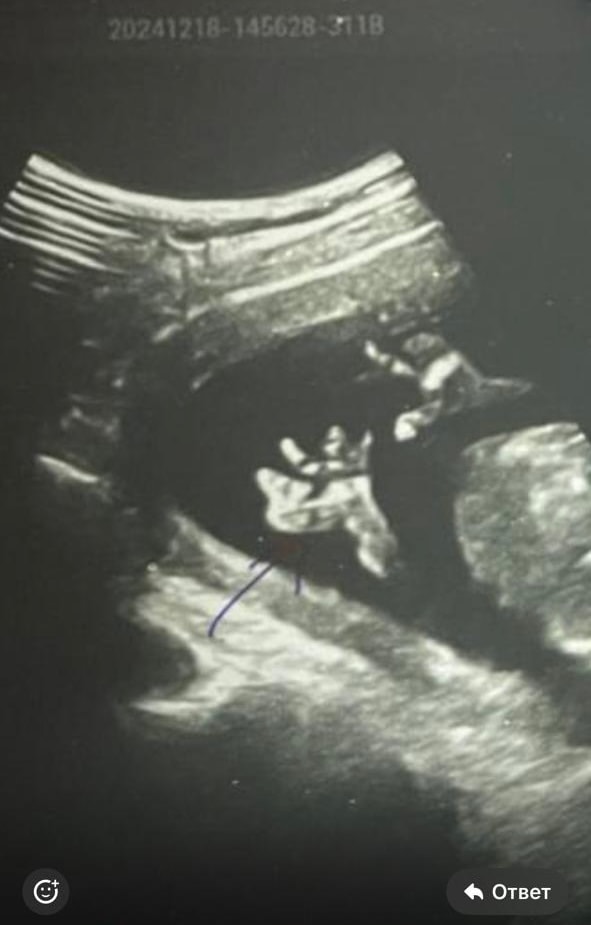

Уютная, это называется «удобно лежит». Пациент пришел с определенным запросом. Как увидели, так и написали. На УЗИ и игра теней может быть, и искаженная визуализация и что угодно еще. У меня тоже есть несколько фото стоп с УЗИ. А вот ручки порой малыш не давал рассмотреть. Он подгибал их к шее, пальчики вообще не видны были. Изображение И фиг вам, а не ладошка и пальчики. Вторая ручка под попой, на том УЗИ тоже не рассмотрели.

Tatiana, вот где пальцы одной длины, это в Ставрополе делали на экспертнике, остальное Ростов, вот такие диагнозы мне ставили фото где все слиплось это в ПЦ смотрели, когда синдактилию поставили Последнее фото, узи за очень дорого в Ростове Я думаю, что давать оценку как видит врач не стоит, но в данном случае, я очень рада, что супер модный эксперт и спец в своем деле ошибся Изображение Изображение Изображение